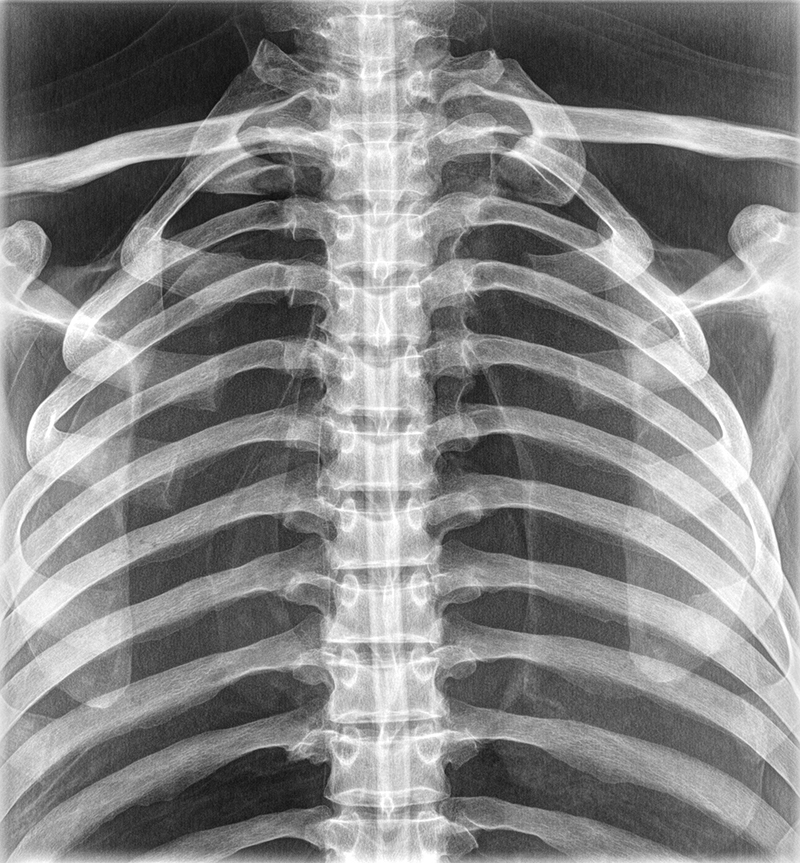

Dieses weltweit einmalige Phantom bietet erstklassige Übungsmöglichkeiten für die Lagerungs- und Einstelltechnik in der Projektions-Radiographie und gehört eigentlich zur Grundausstattung jeder Röntgen-Ausbildungsstätte. Das Phantom enthält ein natürliches menschliches Skelett sowie die Umrisse von Kehlkopf, Lunge, Herz und Nieren (Organe erscheinen als Schatten auf den Röntgenbildern), dadurch können mit dem Phantom echte Röntgenaufnahmen wie beim Patienten gemacht werden. Durch die Verwendung des echten Skeletts können Leitstrukturen im Knochen erkannt werden, was bei Kunststoffskeletten nicht möglich ist. Bei der Montage des Phantoms wird besonderer Wert auf die Darstellung der Gelenkspalte gelegt. Die Gelenke sind voll beweglich montiert, und ermöglichen die Lagerung in den normalen Röntgenpositionen (z.B. Froschposition, Pro- und Supination des Unterarms). Die Arme können nach oben bewegt werden, so dass das Modell auch für alle knöchernen Untersuchungen im CT verwendet werden kann. Bei jedem Phantom handelt es sich um ein handgefertigtes Unikat, welches sich in Größe und Ausführung unterscheiden kann. Je nach Modell können pathologische Befunde vorhanden sein, die äußere Erscheinung kann sich je nach Größe des Modells unterscheiden. Die neue Ausführung dieses Modells wurde in Zusammenarbeit mit einer namhaften deutschen Schule für Med. Techn. Radiologieassistenten komplett überarbeitet und erfüllt alle Anforderungen für die Ausbildung. Der Verkauf dieses Phantoms erfolgt nur gegen Nachweis der medizinischen Verwendung. Natürliche Größe.